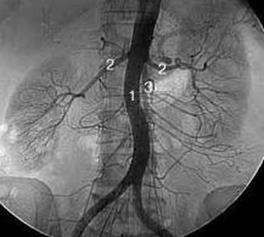

коронарография

Мал. 3. Аневризма аорти

vascularsurgery14

Мал. 4. Аортографія

Коронарографія (мал. 3). Рентгеноконтрастний метод дослідження – найточніше дослідження коронарних артерій. У діагностиці ішемічної хвороби серця ангіографія займає провідне місце. Метод визначає локалізацію тромбу, атеросклеротичної бляшки, дозволяє побачити локалізацію і ступінь звуження гілок судин. Коронарографія визначає необхідність операції. Дозволяє планувати тактику подальшого лікування.

Аортографія (мал.4). Сучасний точний метод дослідження судинної системи людини – аортографія. Комплексне вивчення аорти на рентгенівському апараті проводять після заповнення контрастною речовиною. Методики різняться залежно від виду процедури: аортографію серця застосовують у разі порушення кровообігу, вад і пухлин. Грудною аортографією діагностують відгалуження аорти, захворювання легень, середостіння. Аортографію черевного відділу застосовують для дослідження печінки, сечового міхура, кишечника, матки, селезінки. Ниркову аортографію використовують для діагностування кіст, пієлонефриту, раку.

Процедуру проводять натщесерце. Напередодні ввечері пацієнт очищає кишечник за допомогою клізми. Перед дослідженням перевіряють, чи є алергія на контрастну речовину. Потім роблять місцеве знеболення. Під час процедури роблять прокол стегнової, променевої або пахвової артерії. Всередину судини вводять провідник, через який вставляють катетер. Після вилучення провідника катетер просувається в аорту під контролем рентгену. Під час досягнення судини вводять контрастну речовину – діодон, кардіотраст, гіпак. Одразу після цього роблять низкув знімків, що зберігаються у внутрішній пам’яті комп’ютера. Інформацію можна переносити на флеш-накопичувачі. Під час дослідження людина відчуває тепло. Деякі пацієнти відчувають дискомфорт або нудоту. Після процедури на місце проколу накладають стерильну пов’язку.